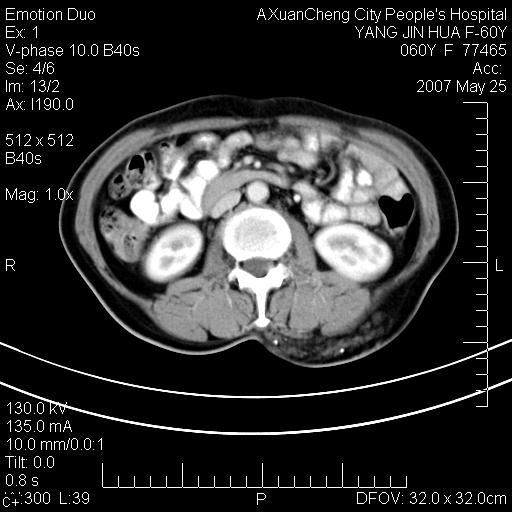

发现左侧腰背部包块40余年,逐渐长大,质软,局部表面可见扩张的血管影

左背部皮下良性肿瘤,密度不均,边界不清,内有脂肪、钙化,增强扫描无明显强化,血管平滑肌脂肪瘤?进一步诊断有困难,建议穿刺活检。

左侧背部皮下混杂密度肿块,结构较疏松,边缘欠光整,内有多发斑点状钙化,考虑:皮下血管瘤。